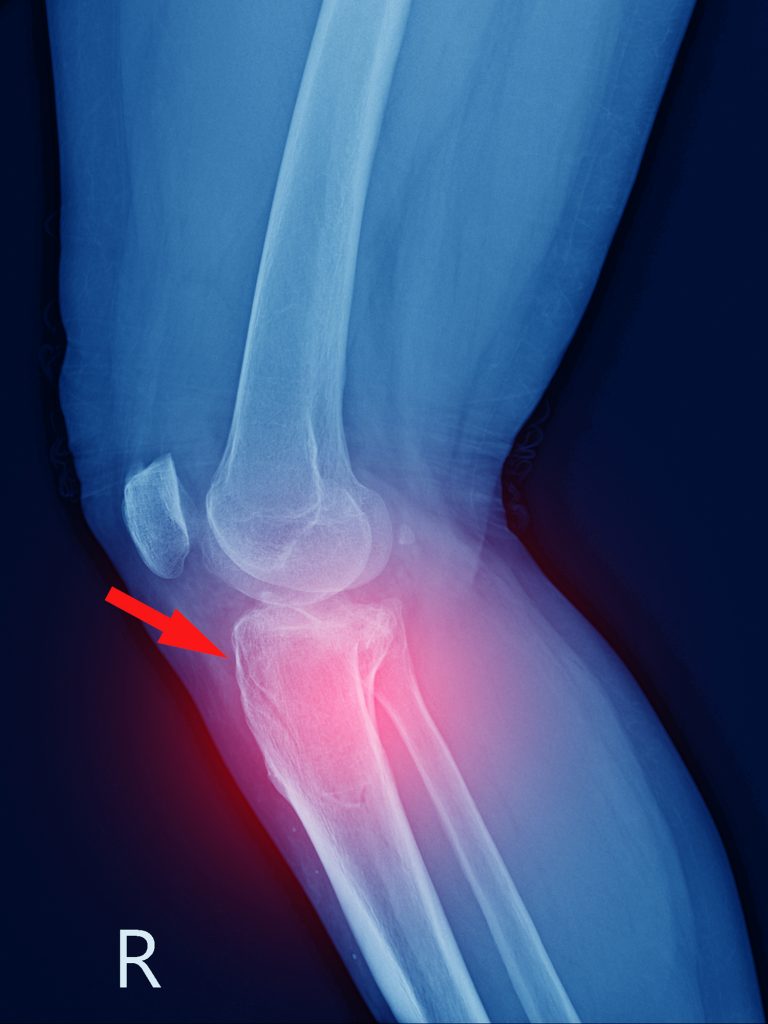

Wśród dzieci w wieku 2-5 lat (choć zdarza się to i starszym) istnieje nawet charakterystyczny uraz, który zdarza się dokładnie w tym momencie. Takie uderzenie powoduje złamanie bliższej nasady kości piszczelowej czyli pęknięcie jej tuż pod kolanem. W optymistycznej wersji to jakieś 3-4 tygodnie w gipsie nad kolano, w pesymistycznej – uszkodzenie chrząstki nasadowej i zatrzymanie wzrostu nogi lub jej zniekształcenie.

– U dzieci dotyczy to złamania lub złuszczenia chrząstki wzrostowej piszczeli, czyli tkanki chrzęstnej mieszczącej się w pobliżu zakończeń rosnącej kości. W skrajnych przypadkach syndrom skutkuje brakiem przyrostu kończyny na długość – tłumaczy dr Maciej Pasieczny z kliniki Carolina Medical Center.